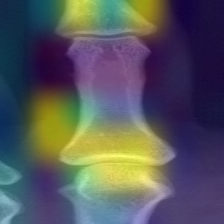

Refer to caption

(a) Feet finger

Figure 4: Attention weights corresponding to various joints while predicting narrowing scores from extracted fingers and wrists from the radiographs, yellow regions demonstrate the region where the model assigns higher weights in the input image

In Fig. 5(a), and 5(b), the joint region in the feet and hand fingers is activated to provide the final predictions, similarly, we see that in Fig. 5(c), all wrist joints are given a higher weightage by the model while making the predictions. Our attention map provides an inbuilt explanability component which can aid the radiologist to believe in the model predictions.